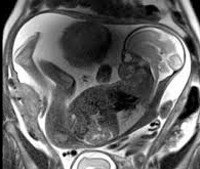

Магнитно-резонансная томография плода. Получение качественных изображений плода с использованием высокотехнологичных методов, в основе которых лежит использование радиомагнитного излучения, не оказывающего вредного воздействия на ткани. Преимущество магнитно-резонансной томографии заключается в отсутствии ионизирующего излучения, высокой контрастности тканей, получении многоплоскостного и трехмерного изображения плода независимо от его положения и гестационного возраста. Назван случай, когда результаты ультразвукового скрининга выявили пороки развития плода, врожденные и генетические заболевания, патологию плаценты и пуповины. Это позволяет рассмотреть область интереса в мельчайших деталях, чтобы сделать прогноз развития плода и его жизнеспособности, выбрать тактику беременности, родов и послеродовой деятельности. Контрастность в диагностическом процессе не используется.

Основой МРТ является метод ядерного магнитного резонанса, который позволяет изучать организм человека на основе насыщения его тканей атомами водорода. Концентрация атомов в разных органах и тканях неодинакова. Мощное магнитное поле, создаваемое томографом, вызывает изменение положения атомов вещества, которое обнаруживается специальным оборудованием. Трехмерное изображение, полученное во время магнитного резонанса плода, может отображаться в нескольких плоскостях, а минимальное расстояние между срезами достигает нескольких миллиметров. Это позволяет выявить также слабо выраженные аномалии развития и небольшие патологические образования. МРТ успешно применяется в неонатологии и гинекологии. В последнее время основным ограничением для применения этой процедуры была двигательная активность ребенка. На сегодняшний день решение проблемы было найдено в виде сверхбыстрых томографов нового поколения. Магнитно-резонансная томография плода с использованием современного оборудования позволяет просматривать «изображение» менее чем за 1 секунду и выбирать любую удобную плоскость сканирования.

Во время процедуры можно детально изучить нервную систему, связки, мышцы, жировую ткань, кровеносные сосуды, паренхиматозные органы и другие анатомические структуры. По результатам МРТ плода определяется количественный и качественный состав околоплодных вод, размеры, положение, структура и контуры плаценты. Положение и тип представления ребенка оценивается с помощью томографии, объем головы измеряется с помощью структур головного мозга.

При визуализации органов брюшной полости определяются их расположение и размеры, а также соответствие полученных показателей гестационному возрасту. МРТ исследования плода приводит к подготовке заключения специалиста, отражающего все изменения в письменной форме. На основании этих данных, клинической картины и результатов других диагностических процедур лечащий врач может поставить окончательный диагноз, составить план лечения или задать вопрос о прерывании беременности.